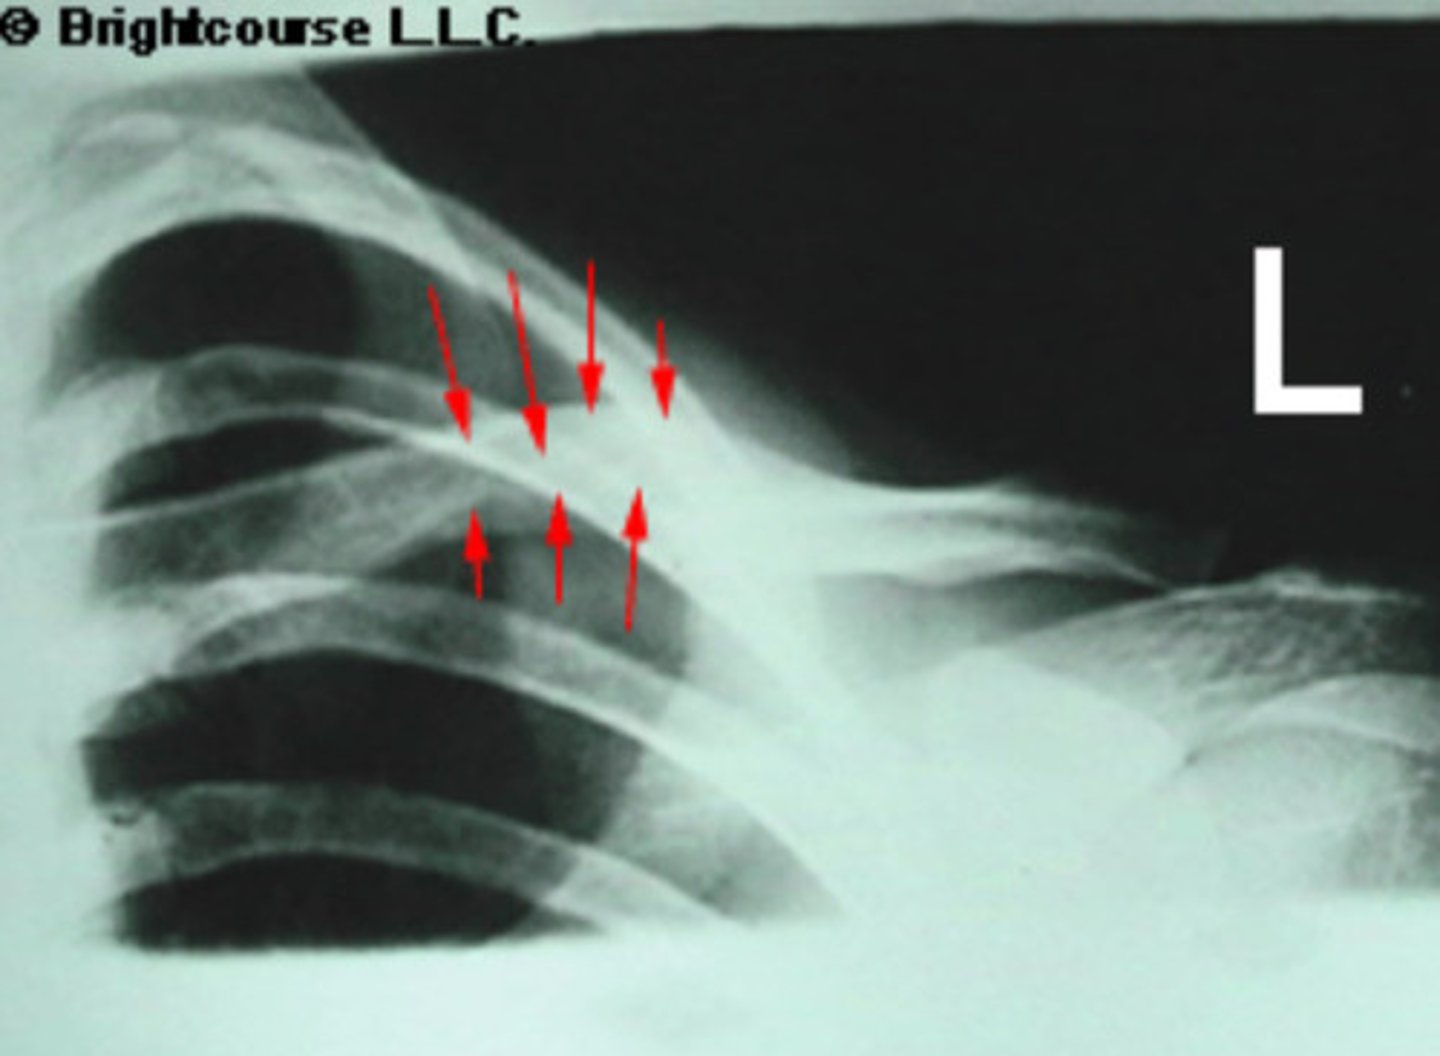

Deltoid tuberosity

What is being pointed out by the arrows in the image?